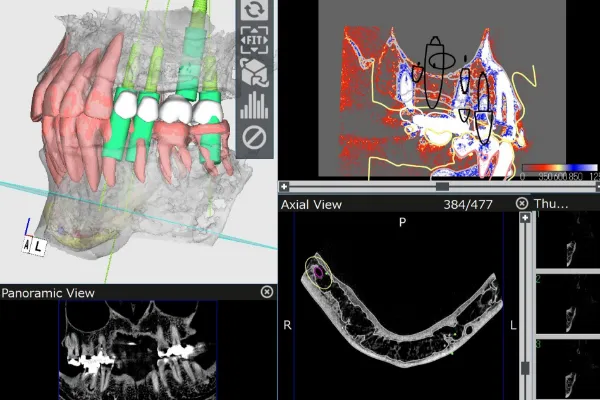

CTスキャンを活用し、

患者様の口腔内を3Dモデル化

えみは総合歯科のインプラント治療は、CTスキャンで口腔内の3Dモデルを作成し、コンピュータシステム「ビオナ」を使用して歯の状態を正確に解析・診断します。

専門医とコンピュータから、精密なインプラント挿入の治療計画を作成します。機械技術と医師の腕が合わさり、患者様の手術への不安や負担を軽くして、手術(インプラント埋め込みの位置・角度)の誤差も従来のものと比べて格段に下がり、ミリ単位の誤差に抑える安全正確な手術になっています。

インプラント治療は体に負担のかかる手術を行うため、綿密な治療計画を立てた上で実行いたします。治療計画は丁寧に患者様にご説明・ご納得いただいた上で進めてまいります。

また、治療はサージカルガイドというインプラントの埋入位置の誤差をなくすためのガイドを利用します。これにより、歯ぐきを最小限もしくは全く切開せずにインプラントの埋入が可能なため手術後の腫れ、痛みが非常に少ないです。

当院では、インプラント手術を行う前の精密検査で通常の歯科用レントゲンだけでなく、CTスキャンの骨の情報とお口の型取りによる歯肉の粘膜の情報をコンピュータ上で統括してシュミレーションを行うことで加えて骨の内部の神経の走行を把握した上で、安全に治療を行なっていますのでご安心ください。

こちらに関しても、CTスキャンによるシュミレーションを行い位置の把握ができますので、当院ではこのようなことが起こることはありません。

こちらに関しても、CTスキャンによるシュミレーションを行い位置の把握ができますので、当院ではこのようなことが起こることはありません。